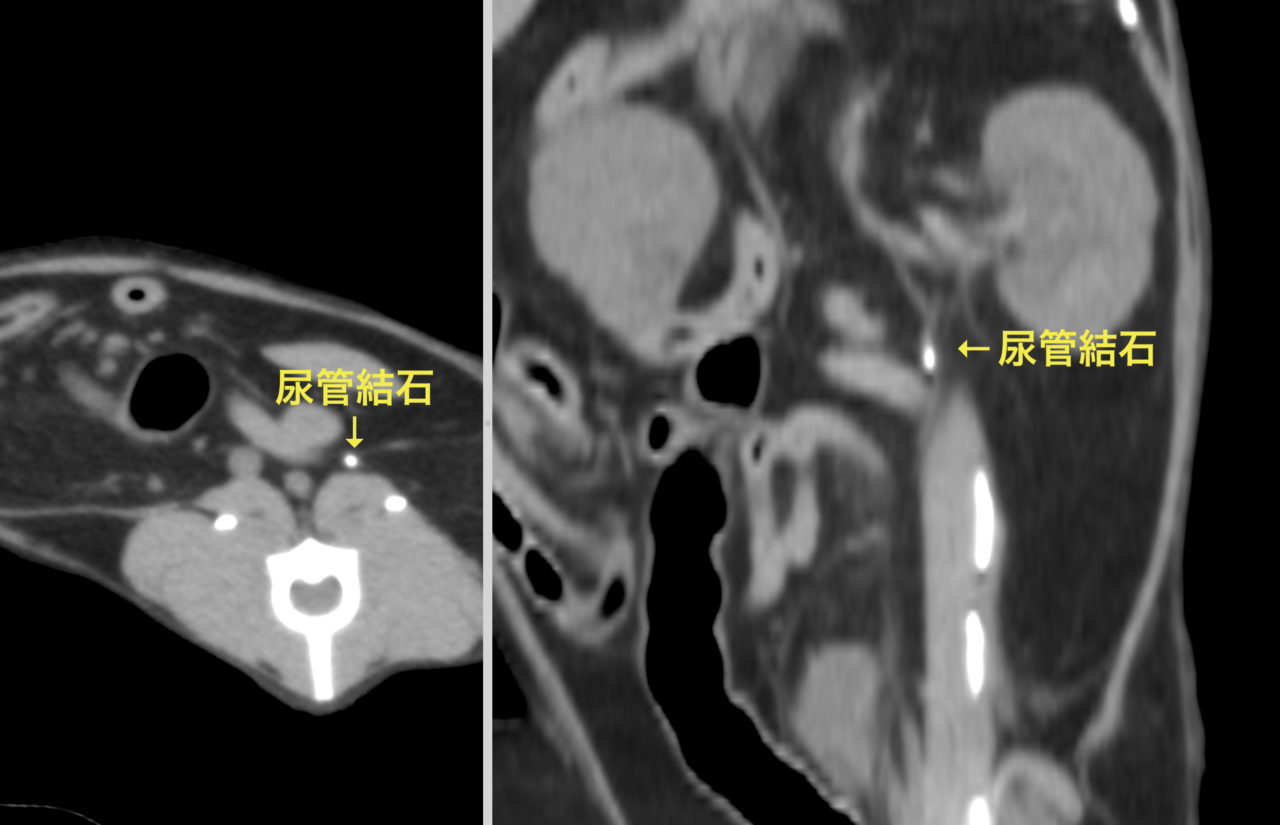

猫さんの尿管に結石がつまって腎臓の数値が上昇してきており、なんとかしてほしいと主治医から連絡がありました。マイクロサージェリーで結石を摘除し、尿管膀胱新吻合術を行いました。尿管は結石により炎症を起こしていたので術後の吻合部位に狭窄が生じることがあります。今回は短尺型尿管ステントを留置しています。これでたくさんおしっこが出るようになります。